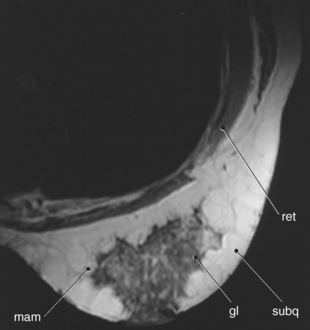

The female breast, or mammary gland, lies within the subcutaneous tissue overlying the pectoralis major muscle. Typically the breast extends laterally from the sternum to the axilla and inferiorly from the second to the seventh ribs. For examination purposes, the breast can be divided into four quadrants (upper inner, upper outer, lower outer, lower inner) and the tail of Spence (Figure 6.117). The breast consists of three layers of tissue: subcutaneous layer, mammary layer, and retromammary layer (Figure 6.118). The subcutaneous layer contains the skin and all of the subcutaneous fat. The mammary layer consists of glandular tissue, excretory (lactiferous) ducts, and connective tissues. The glandular tissue consists of 15 to 20 lobes arranged radially around a centrally located nipple. The glandular lobes are embedded in connective tissue and fat, which give the breast its size and shape. Excretory (lactiferous) ducts extend from each lobe to the nipple, where they terminate as small openings. Cords of connective tissue coursing throughout the mammary layer, from the dermis to the thoracic fascia, are known as the suspensory ligaments of the breast or Cooper’s ligaments. These ligaments provide support for the breasts. The retromammary layer contains muscle, deep connective tissue, and retromammary fat (Figures 6.119 and 6.120).

Figure 6.119 Sagittal, T1-weighted MR scan of female breast.

Key: pec, Pectoralis major muscle; ret, retromammary layer; mam, mammary layer; subq, subcutaneous layer; gl, glandular; n, nipple.

Figure 6.120 Axial, T1-weighted MR scan of female breast.

Key: ret, retromammary layer; mam, mammary layer; subq, subcutaneous layer; gl, glandular.